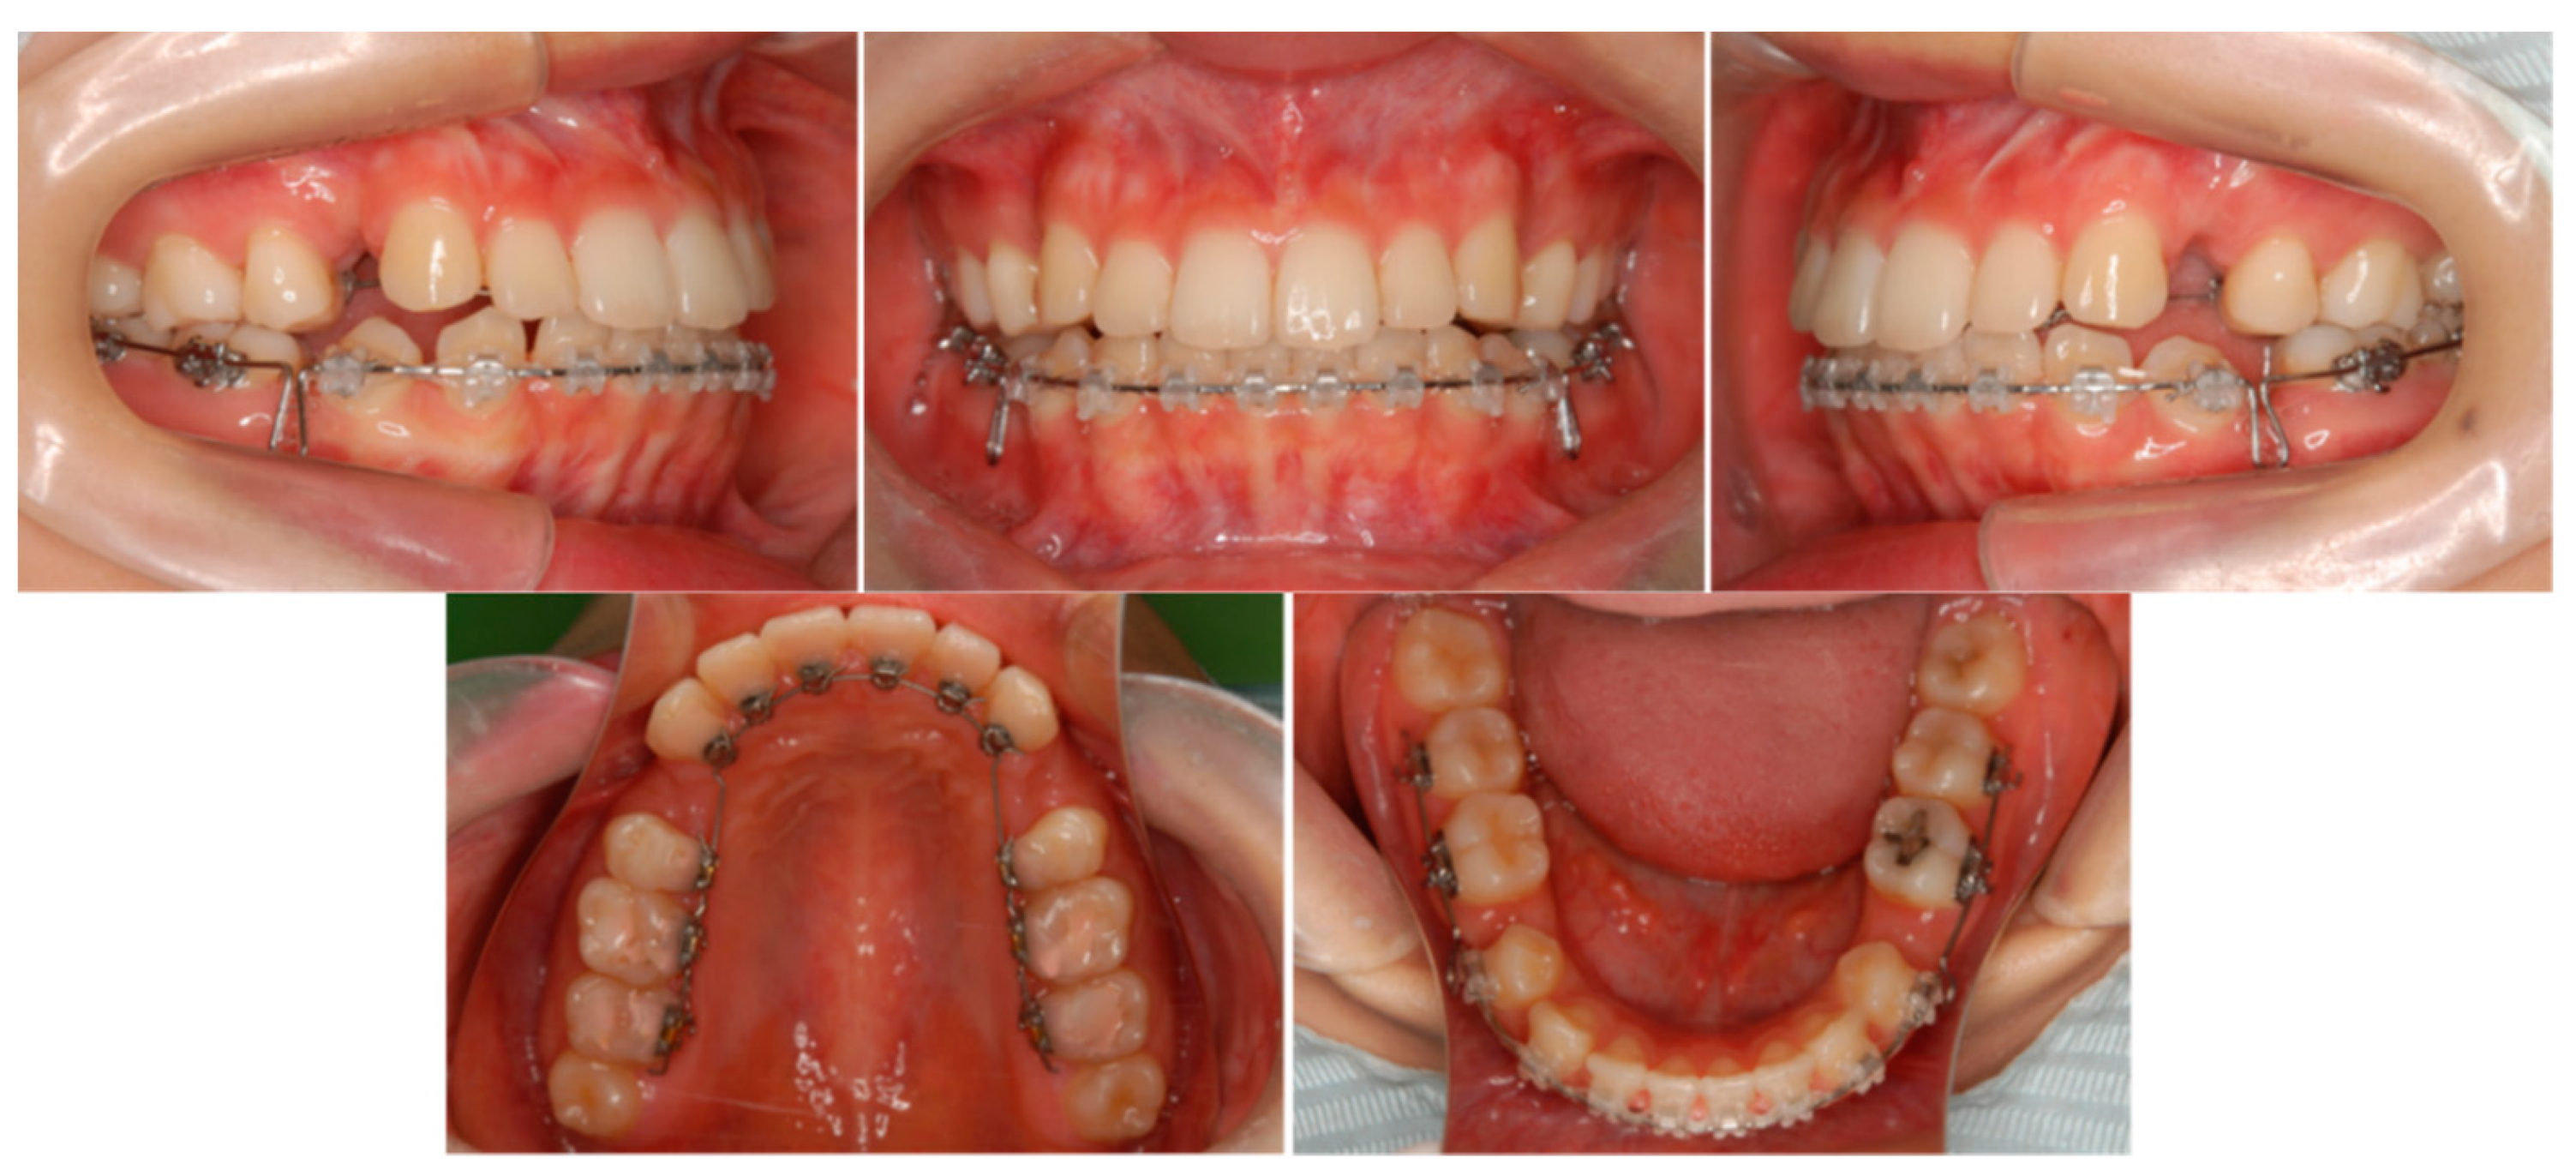

6.4. Treatment Progress